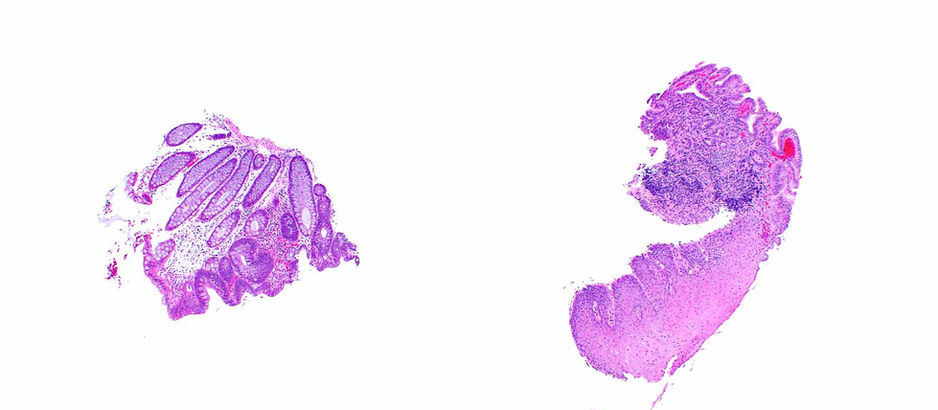

A fragment of a colorectal tubular adenoma ended up in with a sample from the esophagus and was diagnosed as low-grade dysplasia in Barrett mucosa. Indeed the adenoma has low-grade dysplasia but the quality of the mucin is all wrong. Case by Dr. Elizabeth Montgomery, Clinical Professor, Vice Chair of Faculty Development & Mentoring, Director of Surgical Pathology Fellowship Training Program, Co-Director, Pathology Reference Services, and Editor-In-Chief at Innovative Science

Nov 27, 20251 min read